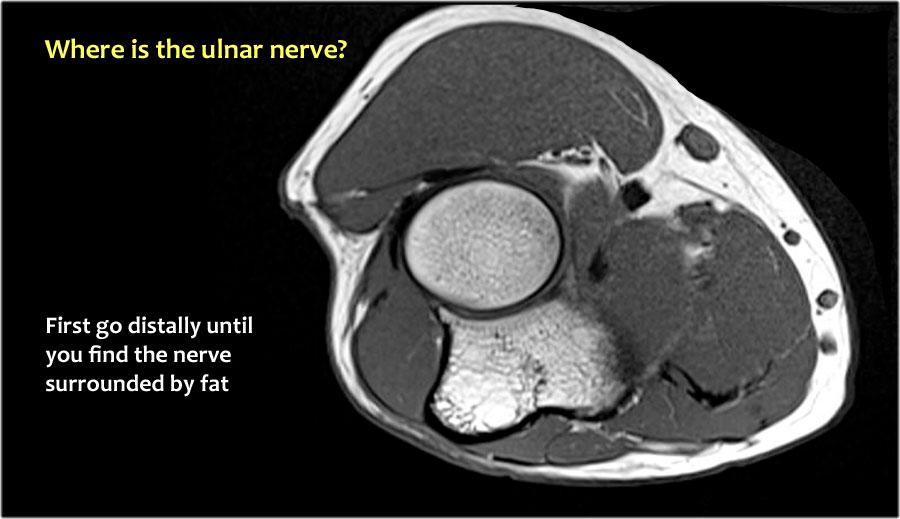

Vì vậy, khi chúng ta quay lại hình ảnh, bạn sẽ nhận thấy rằng có thể khó tìm thấy dây thần kinh.

Bất kỳ cấu trúc dưới da nào trong số này đều có thể là dây thần kinh đã được chuyển vị.

Một cách để thực hiện là đi theo các cấu trúc về phía xa cho đến khi tìm thấy dây thần kinh trụ ở phía xa tại vị trí bình thường của nó ở vùng cẳng tay gần được bao quanh bởi mô mỡ.

Sau đó khi bạn theo dõi nó về phía gần, bạn sẽ nhận thấy rằng đây là một trường hợp chuyển vị dưới da.